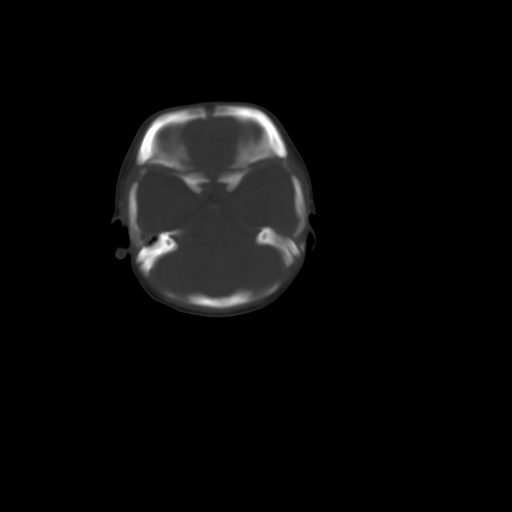

男,12天,自然分娩,其母发现右顶部头皮包块逐渐增大。

右顶部头皮血肿

右顶部头颅血肿(骨膜下血肿)

右顶骨呈膨胀性改变,骨纤维结构不良?

右顶部头皮血肿,可能是产道挤压所致。以后会慢慢恢复。

鉴别:骨膜下血肿,一般为产伤,应用产钳之类的吧

疑问:患儿脑白质密度比较低,基底节区密度比较高,类似于“双圈征”脑沟密度也偏高。该婴儿可有别的异常吗?反射正常吗?评分能达到5分吗?如果正常,就随诊观察吧。不正常要考虑到缺血缺氧性脑病。